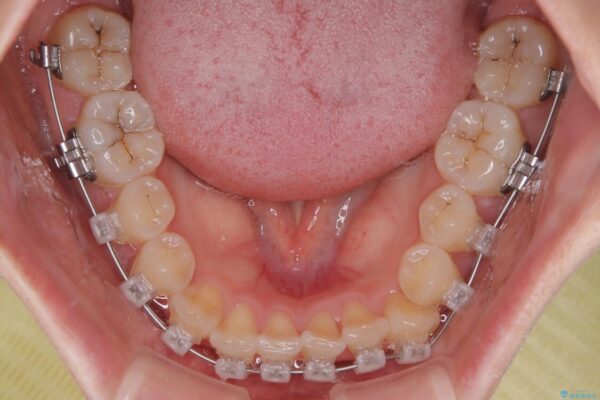

治療途中

• 前歯のねじれ・ガタガタを10か月で改善!20代女性の矯正治療|クリアブラケットでむし歯になりにくい歯並びへ改善 治療途中画像